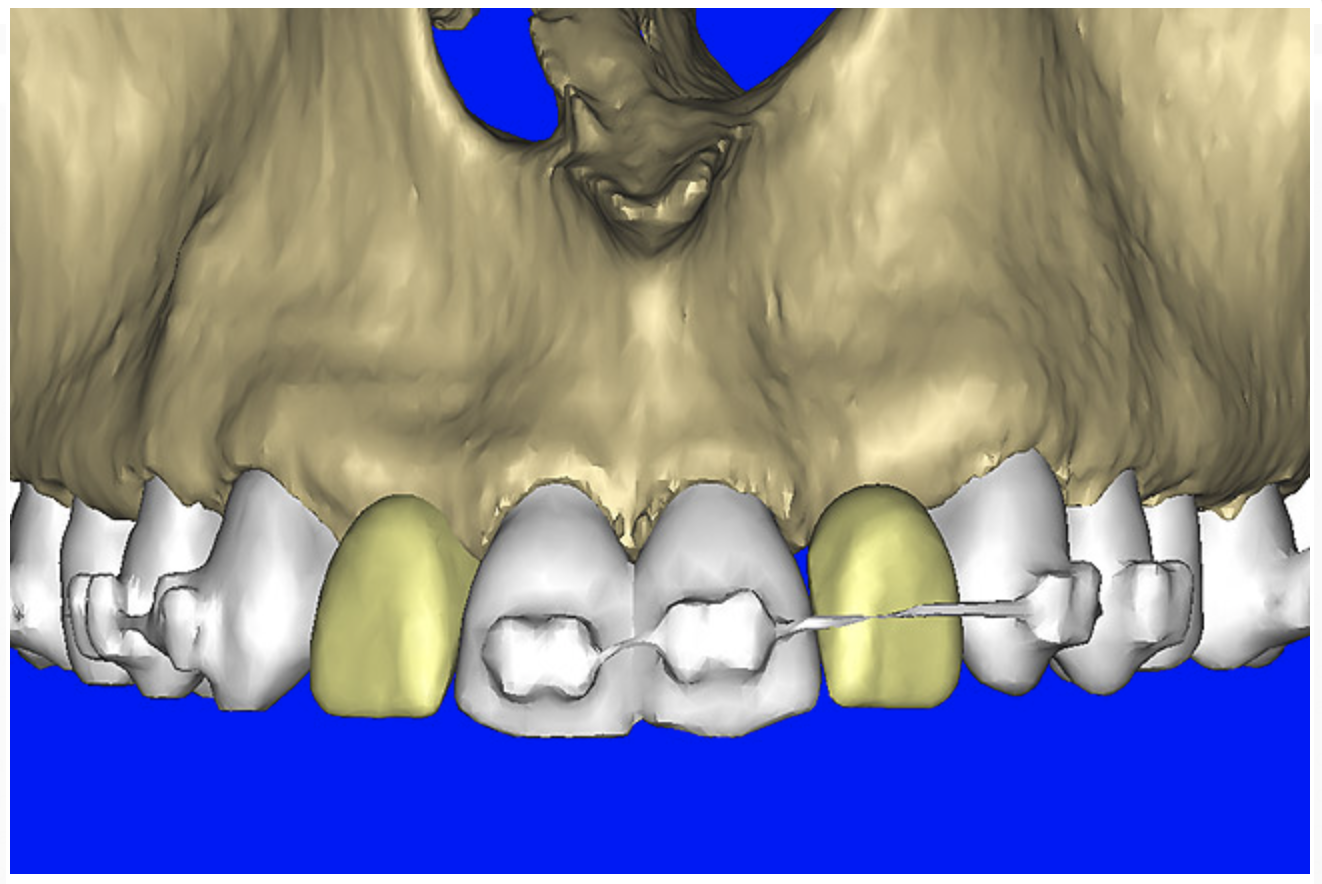

After the basic plan had been established, it was re-evaluated using interactive 3D images. The reconstructed 3D view of the maxilla clearly illustrated the extent of the bilateral facial concavities, and the root eminences of the adjacent and posterior teeth (Figure 7A). The placement of the virtual implants then was evaluated to ensure that the facial cortical plate was not perforated (Figure 7B). The implants were labeled individually as “7” and “10,” with the simulated yellow abutment projection indicating the facial-lingual inclination through the bone to the level above the incisal edge of adjacent teeth. The ability to gain a better understanding of these individual root forms can not be underestimated. The dental literature has suggested certain parameters for placing implants near teeth and implants next to other implants. However, there is little scientific 3D documentation to support these suggested rules.5-10 The use of an interactive treatment-planning software application permits closer scrutiny of previously difficult-to-visualize areas, and can now be used to redefine perceptions of spatial positioning of implants, especially when in close proximity to natural tooth roots, vital anatomy, and adjacent implants.27-29

Figure 7a  The 3D reconstruction showed (A) the facial concavities and root eminences, and allowed (B) for evaluation of virtual implant placement to ensure the facial cortical plate was not perforated.

Figure 7a

Figure 7b  The 3D reconstruction showed (A) the facial concavities and root eminences, and allowed (B) for evaluation of virtual implant placement to ensure the facial cortical plate was not perforated.

Figure 7b